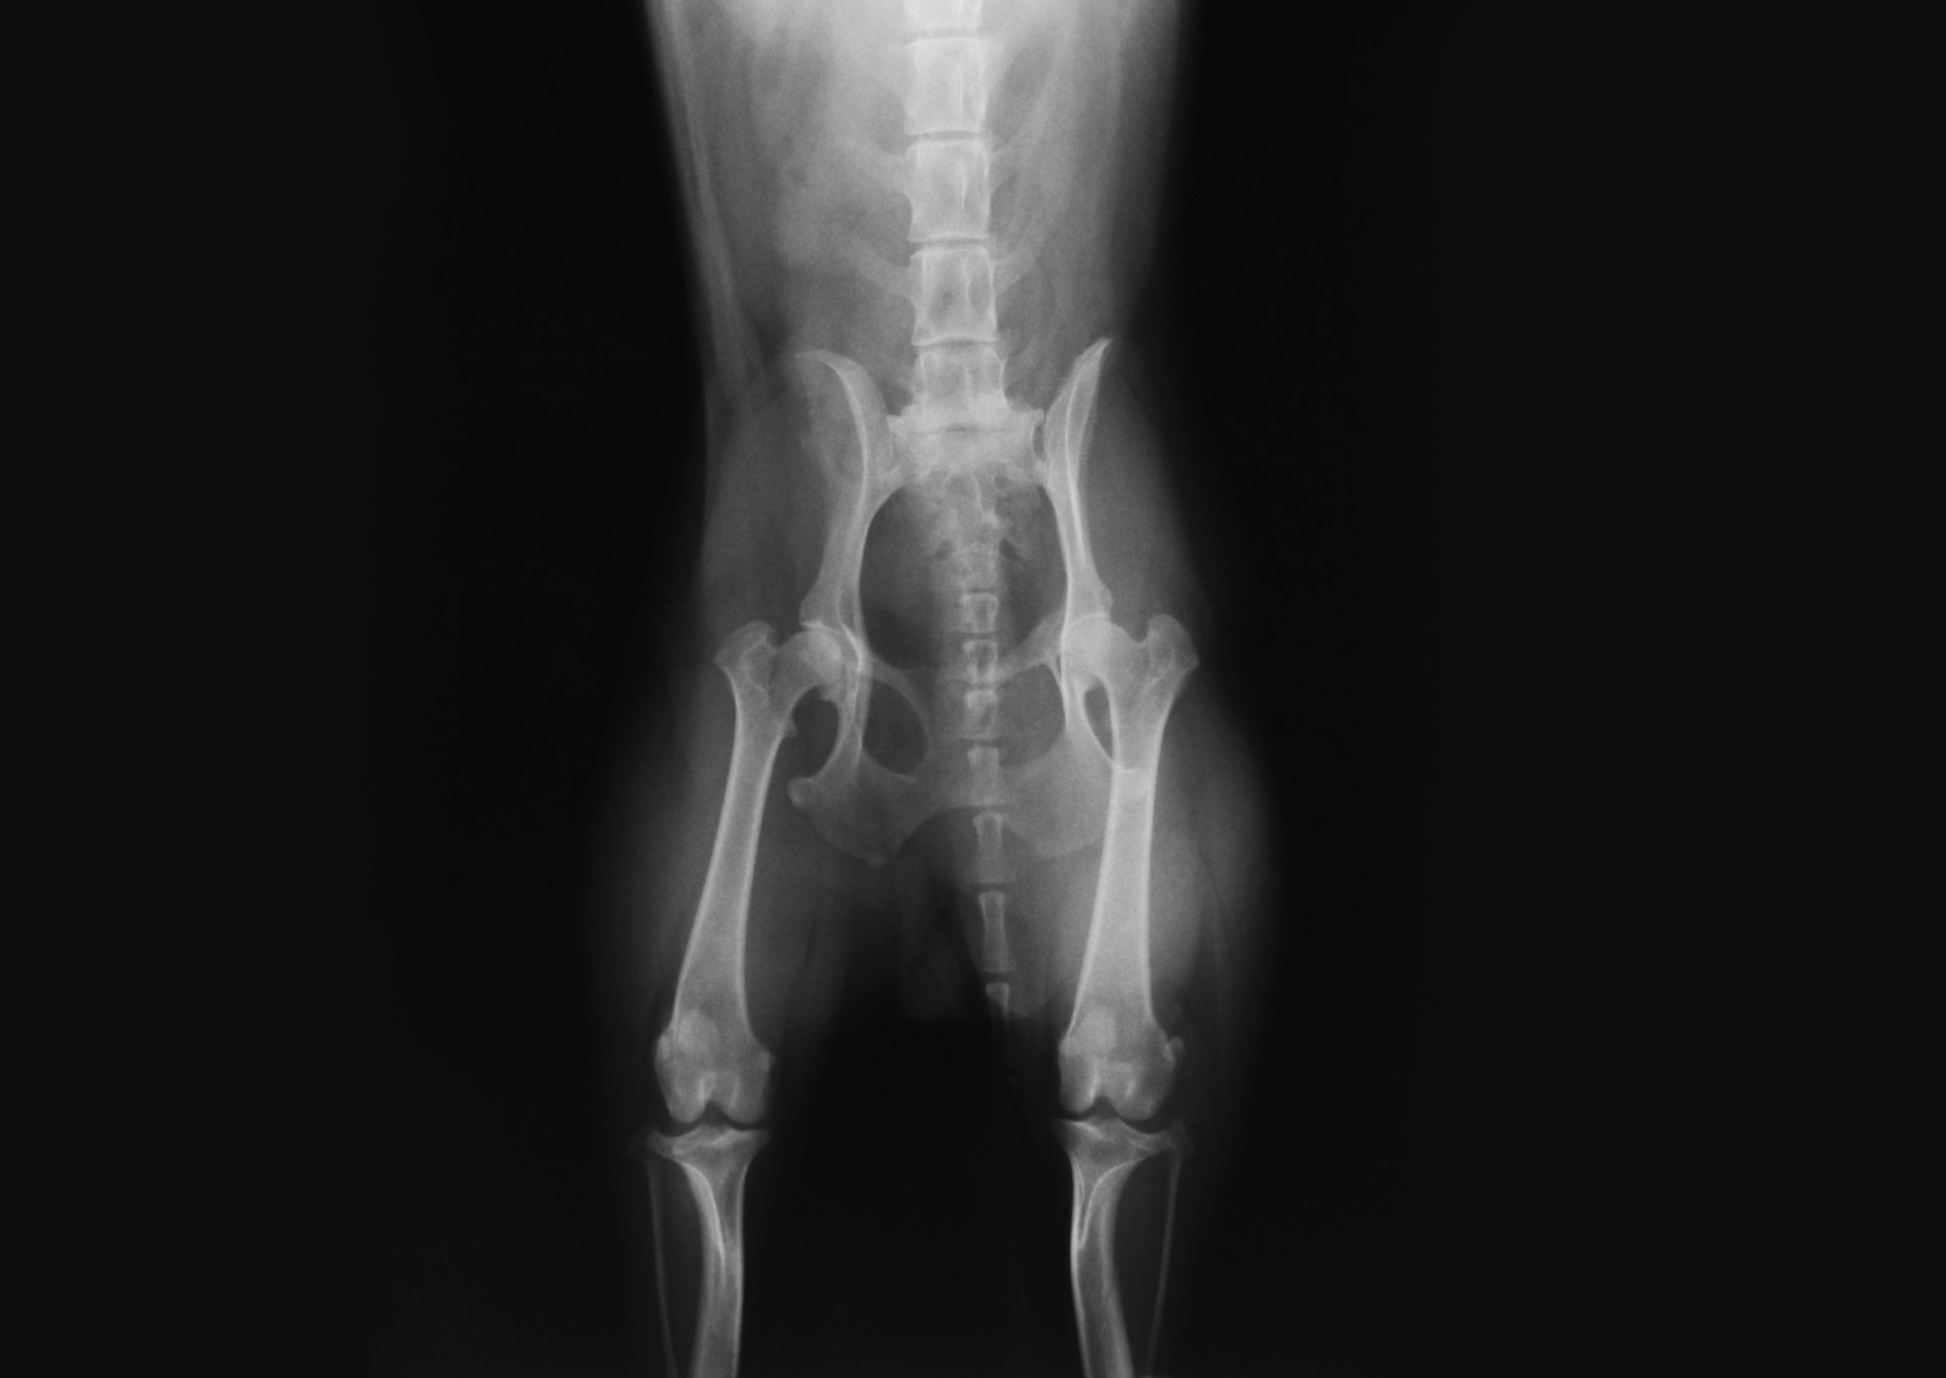

The patient has been appropriately triaged and stabilised. You are aware that hind limb function is impaired. Radiography revealed pelvic fractures. How do you make decisions regarding management of the bony injuries themselves?This presentation guides the first opinion practitioner through imaging, assessment and decision-making regarding orthopaedic pelvic injuries following trauma. The focus will be primarily on ilial and acetabular fractures and sacroiliac luxations.